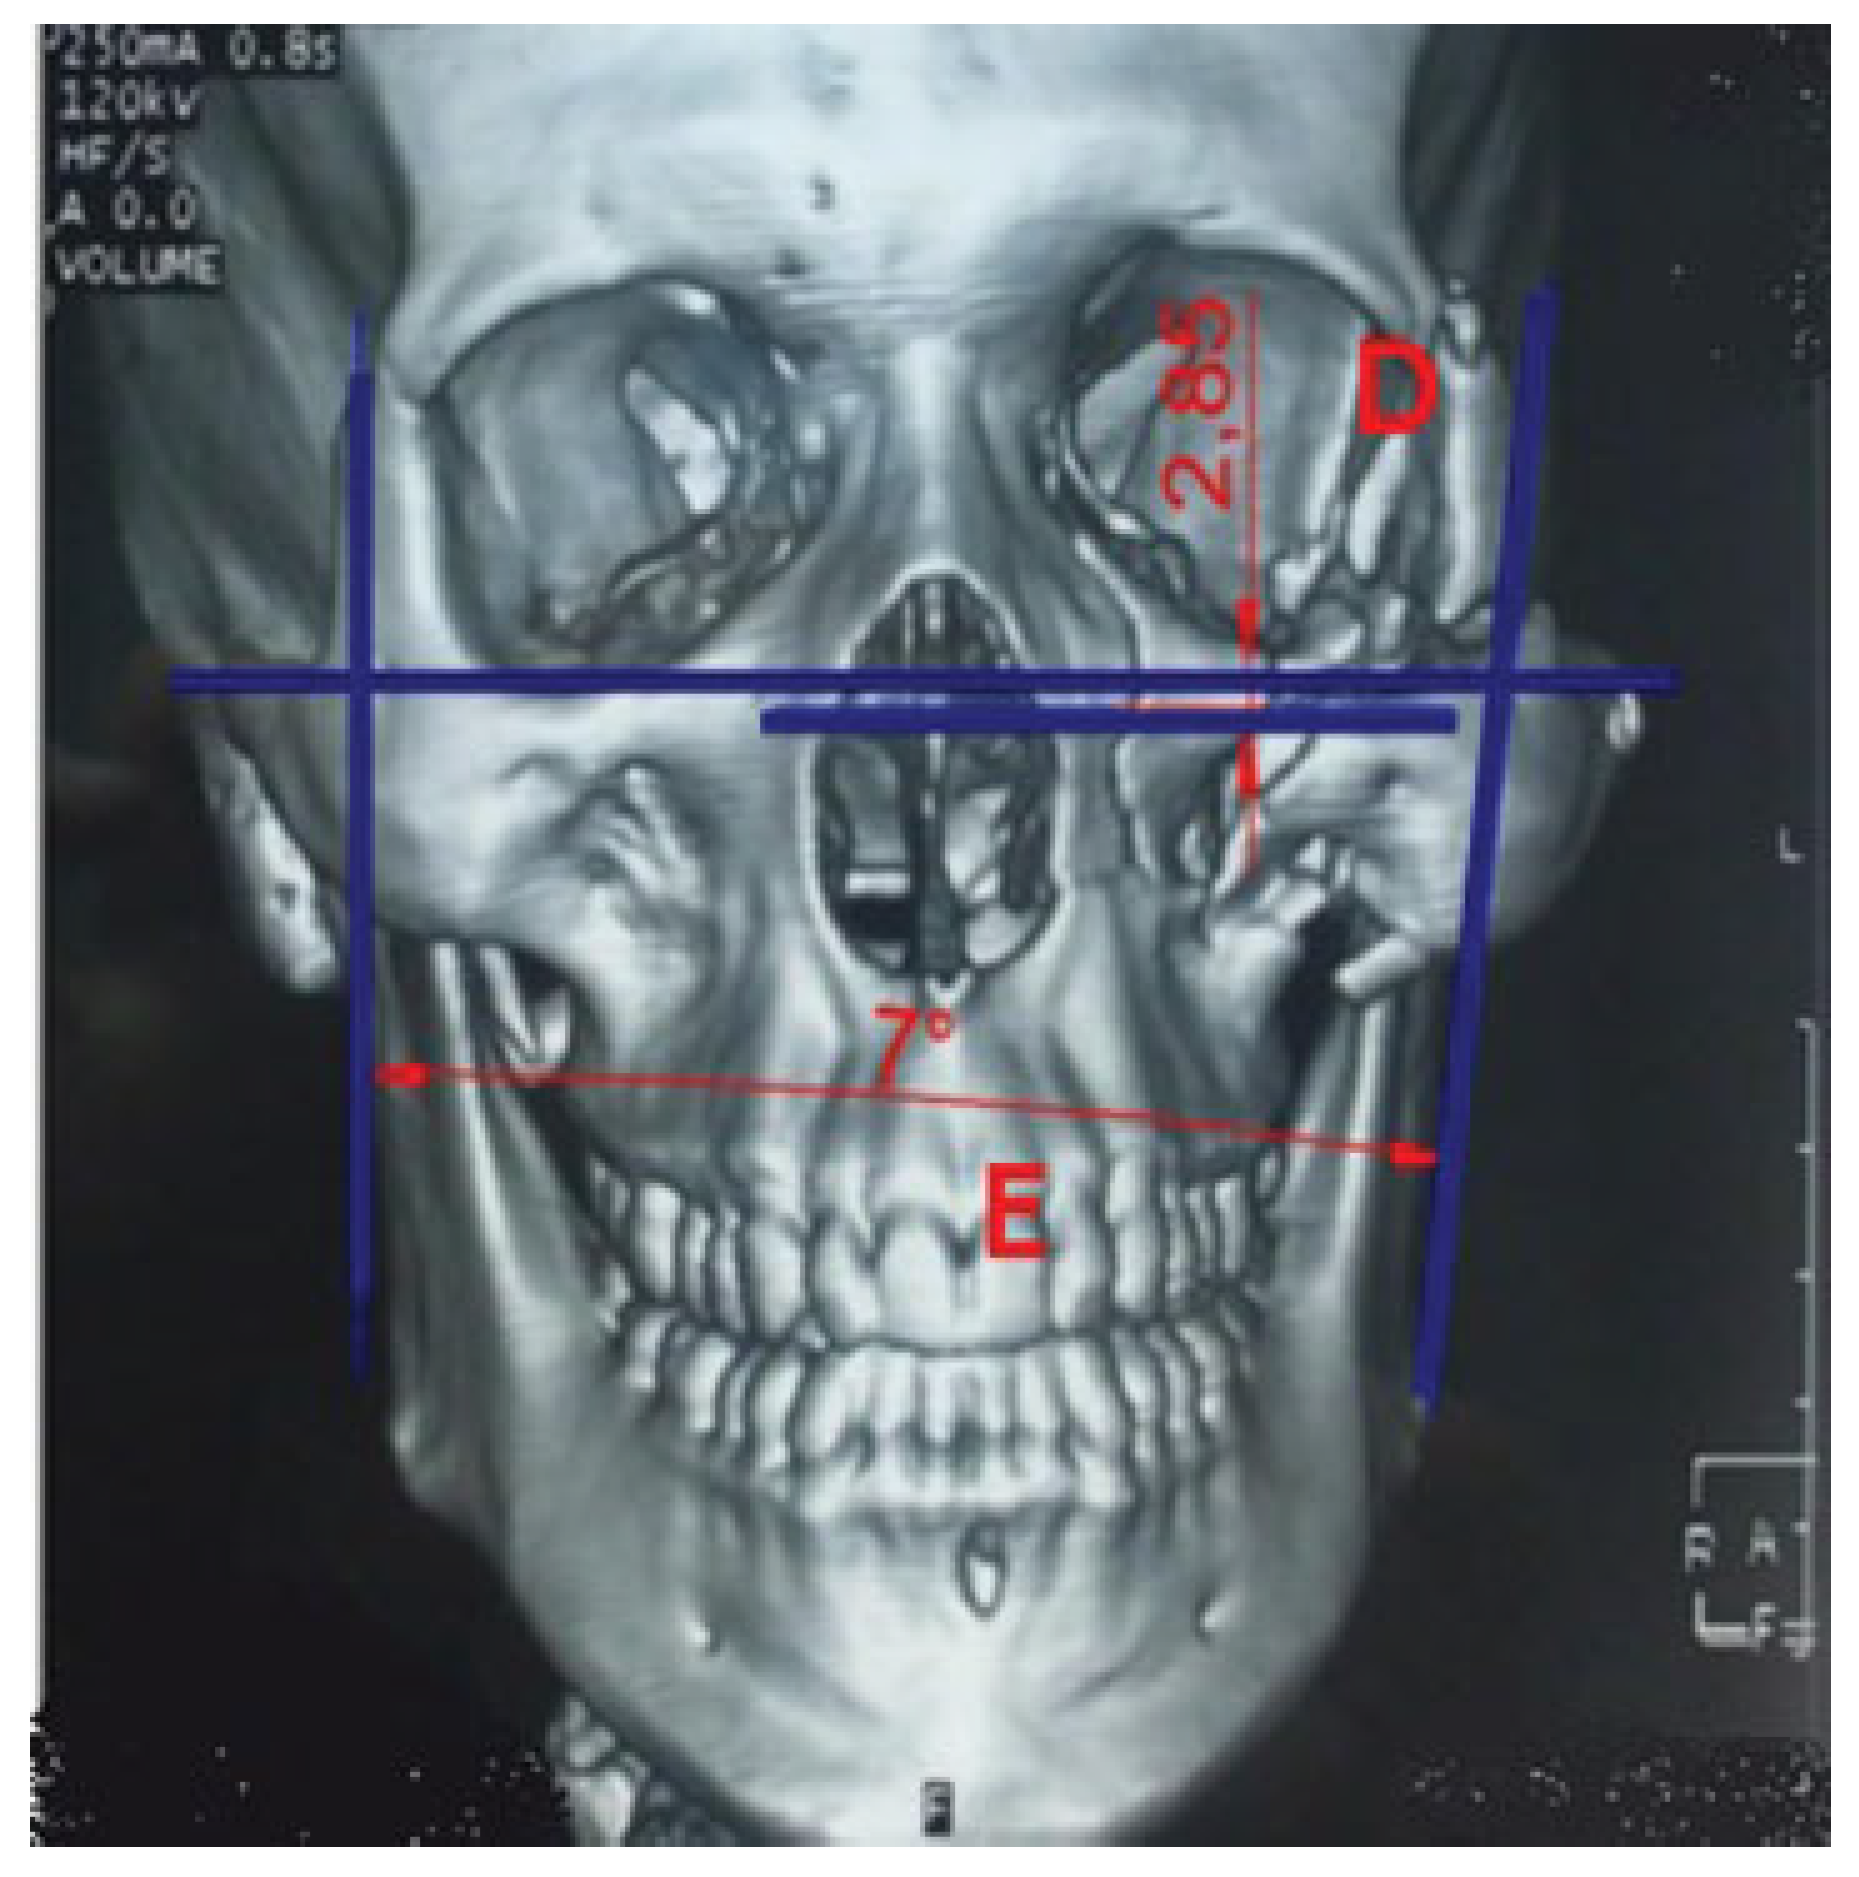

• Zygomatic projection (corresponding to z-axis): Compare the anteroposterior projection of zygoma on both sides at the level of clivus by measuring the distance between the reference line (inter pterygoid line) and center of zygoma (distance A; measurements in cm).

• Zygomatic width (corresponding to x-axis): Compare the lateral presentation of zygoma on both sides at the level of clivus by measuring the distance between the reference line (nasal septum) and center of zygoma (distance B; measurements in cm; Figure 1).[6]

Figure 1. Radiological assessment of zygomatic position in axial view at the level of clivus. Distance A—Zygomatic projection: anteroposterior projection of zygoma forms interpterygoid line (reference line) and center of zygoma (distance A; measurements in cm). Distance B— Zygomatic width: lateral presentation of zygoma from nasal septum (reference line) and center of zygoma (measurements in cm).